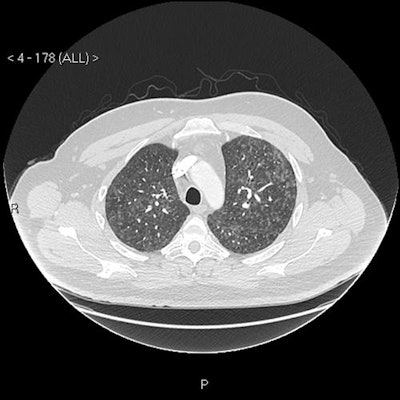

CT scan shows mosaic pattern; apical axial view.

CT scan shows mosaic pattern; middle zones axial view.